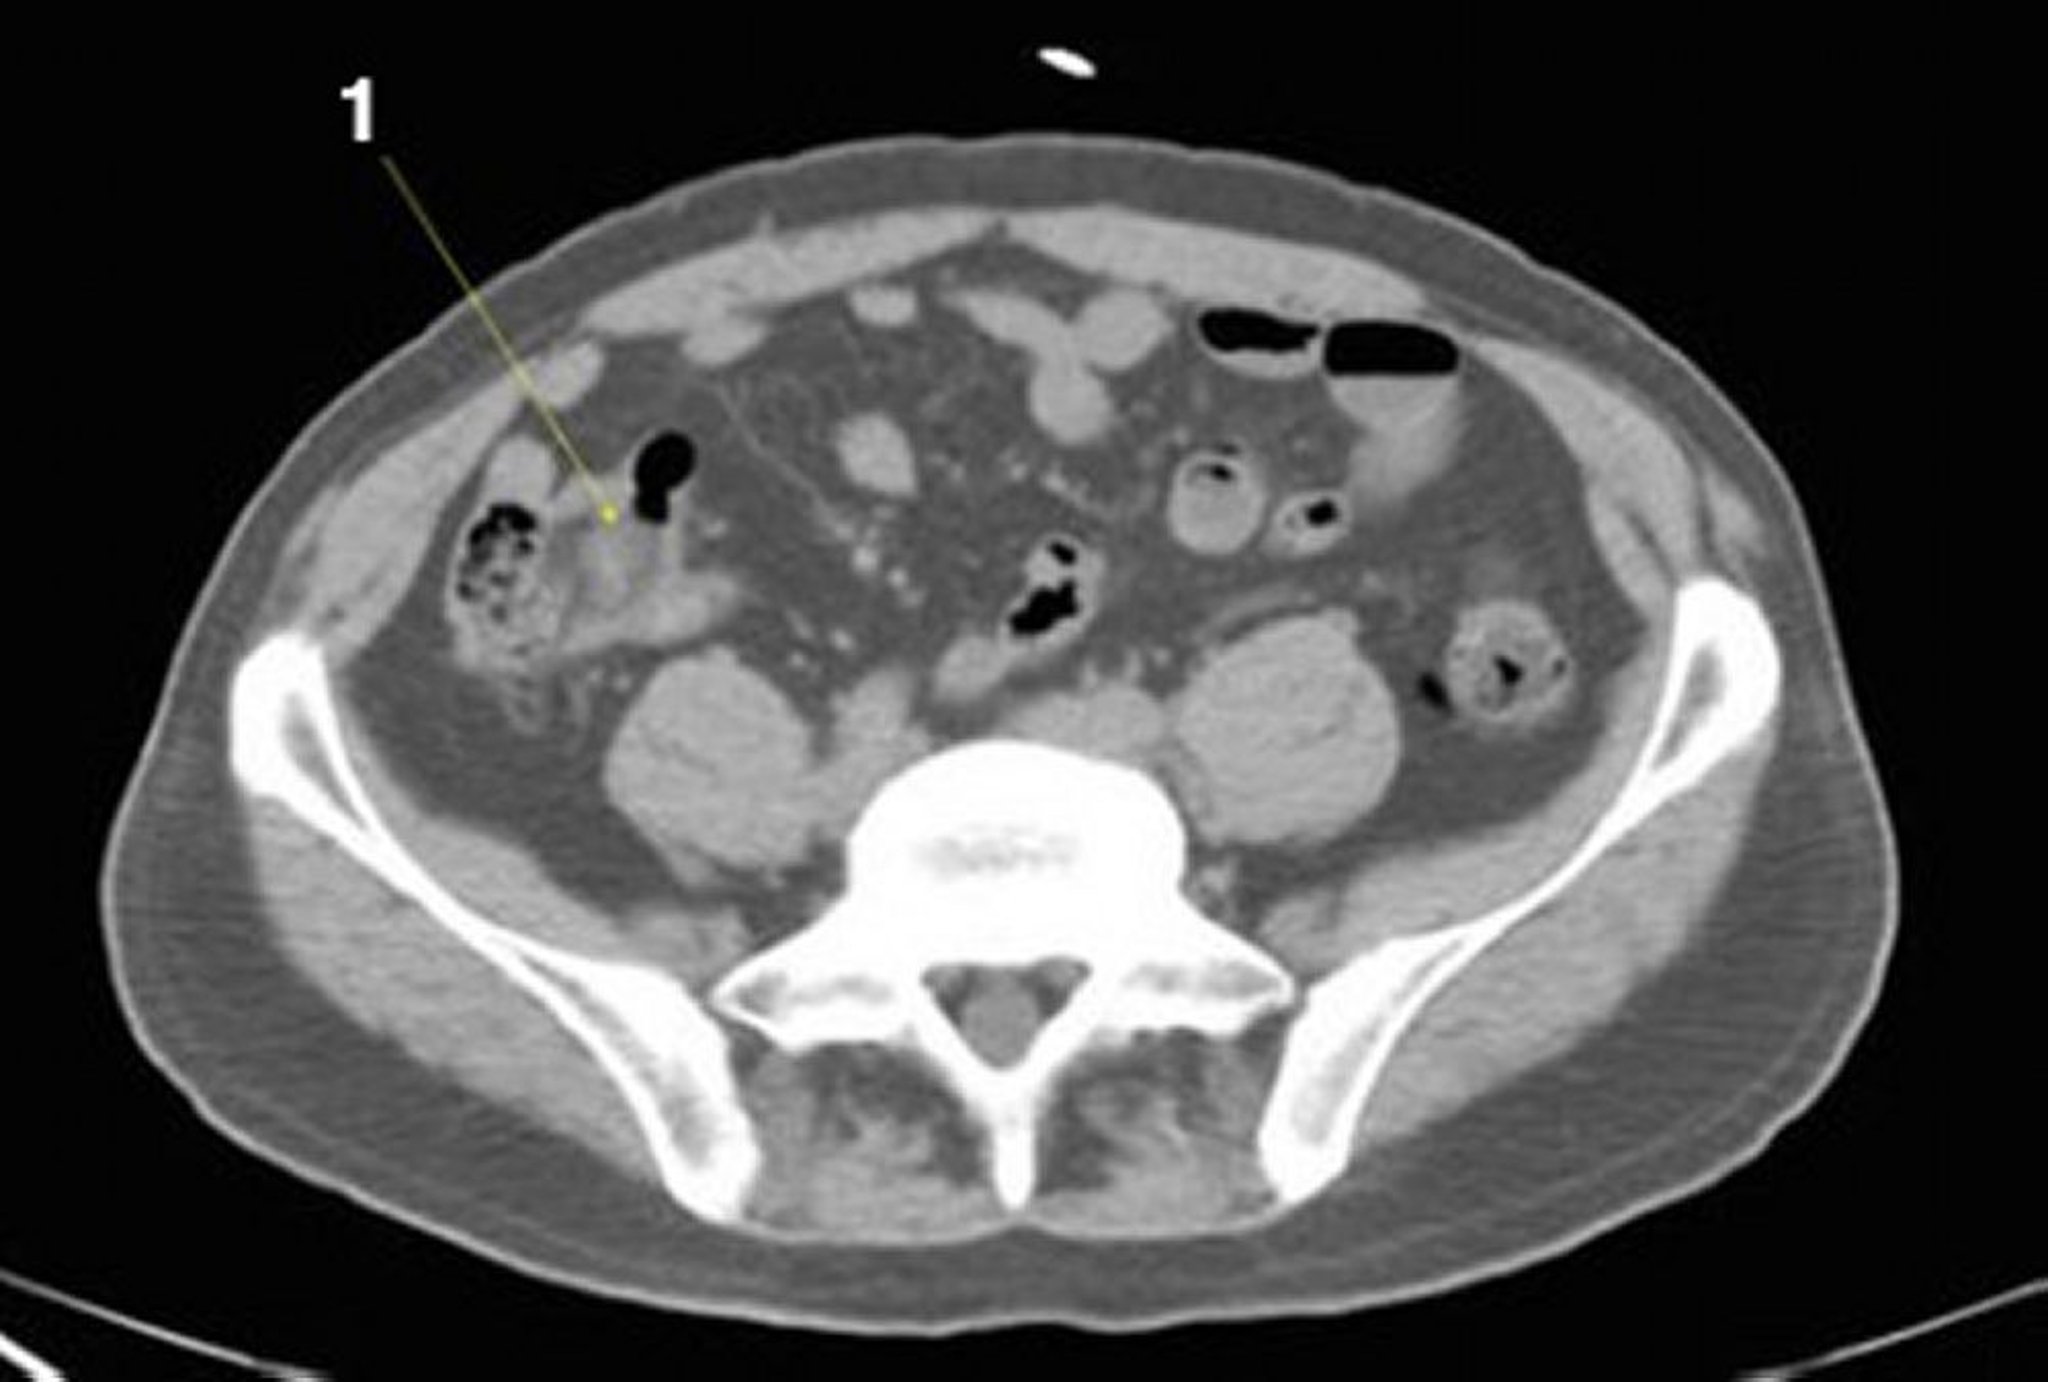

TDM sans contraste de l'abdomen et du bassin montrant une anatomie normale (diapositive 21)

1 = iléon.